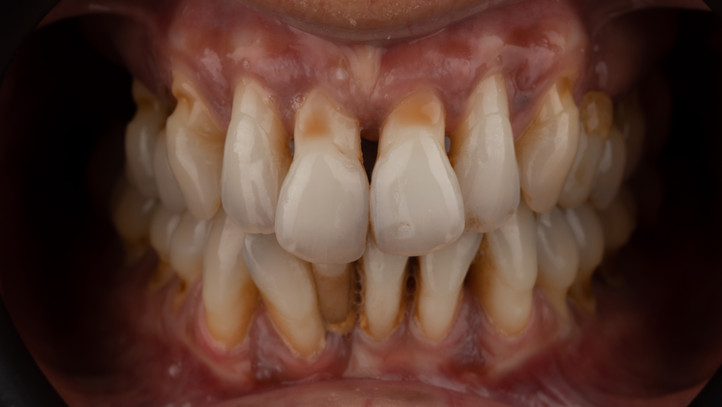

Despite her age, this patient faced a reality that is normally associated with later cases: very advanced periodontitis, with severe loss of bone support and generalized tooth mobility.

The impact was visible — not only on their function, but above all on their self-esteem, well-being and the way they related to others. The smile, which should be light and confident, was often hidden, conditioned by shame and discomfort.